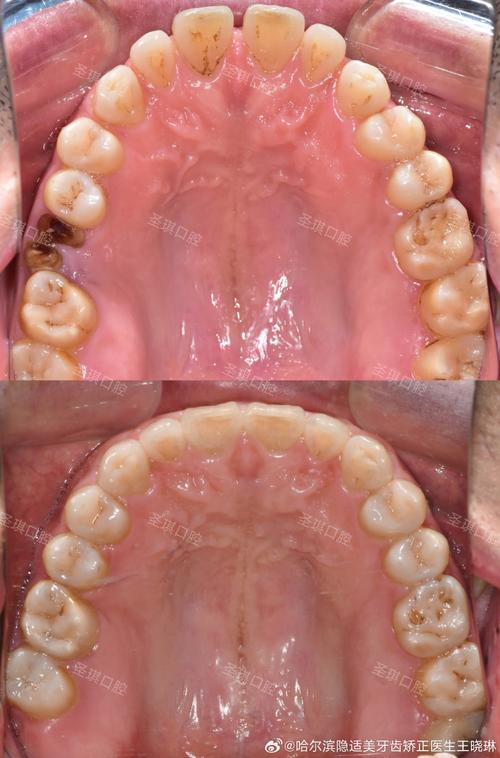

矫正后发现智齿萌出,应该如何应对?关键在于“定期评估,区别对待”,建议矫正结束后每半年进行一次口腔检查,拍摄全景片(曲面断层片),观察智齿的萌出状态、位置方向以及与邻牙的关系,根据临床指南,智齿的处理可参考以下原则:

- 正位萌出且无异常:若智齿完全萌出,位置正常,与对颌牙咬合良好,且无疼痛、龋坏、牙周问题,可暂不处理,但需加强口腔清洁,避免食物嵌塞。

- 阻生或位置不正:若智齿呈近中倾斜、水平阻生等状态,与邻牙间存在间隙或已压迫邻牙牙根,即使无症状也建议预防性拔除,因为矫正后的牙齿排列紧密,智齿的潜在威胁会长期存在,随着年龄增长,牙槽骨骨质变硬,拔除难度和风险也会增加。

- 已引发症状或并发症:若智齿反复引发冠周炎(表现为牙龈红肿、疼痛、张口受限)、邻牙龋坏或牙周袋形成,需立即拔除,避免炎症扩散影响矫正效果。